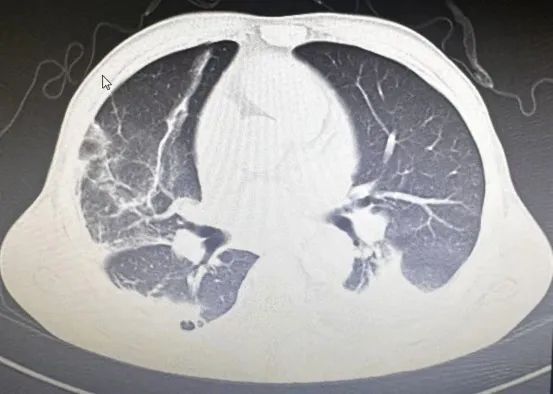

经过治疗,目前患者咳嗽、咳痰等症状已消失,肺部查体未见异常征象,复查患者肺部影像学及炎症指标明显好转,于近日出院。

重症鹦鹉热患者可于短期内出现呼吸衰竭和ARDS等呼吸系统症状。胸部CT检查以炎性病变始于单侧肺下叶多见,加重后累及双侧肺叶,上下肺均可受累,可合并有小片状的磨玻璃影、结节影、实变影和小叶间隔增厚,以胸膜下分布为主,常见“支气管充气征”、“细网格征”,可见“晕征”,常伴有胸腔积液,可伴有肺门及纵隔淋巴结肿大。治疗上常用的Cps抗菌药物包括四环素类、新型四环素类衍生物、大环内酯类和氟喹诺酮类等药物。